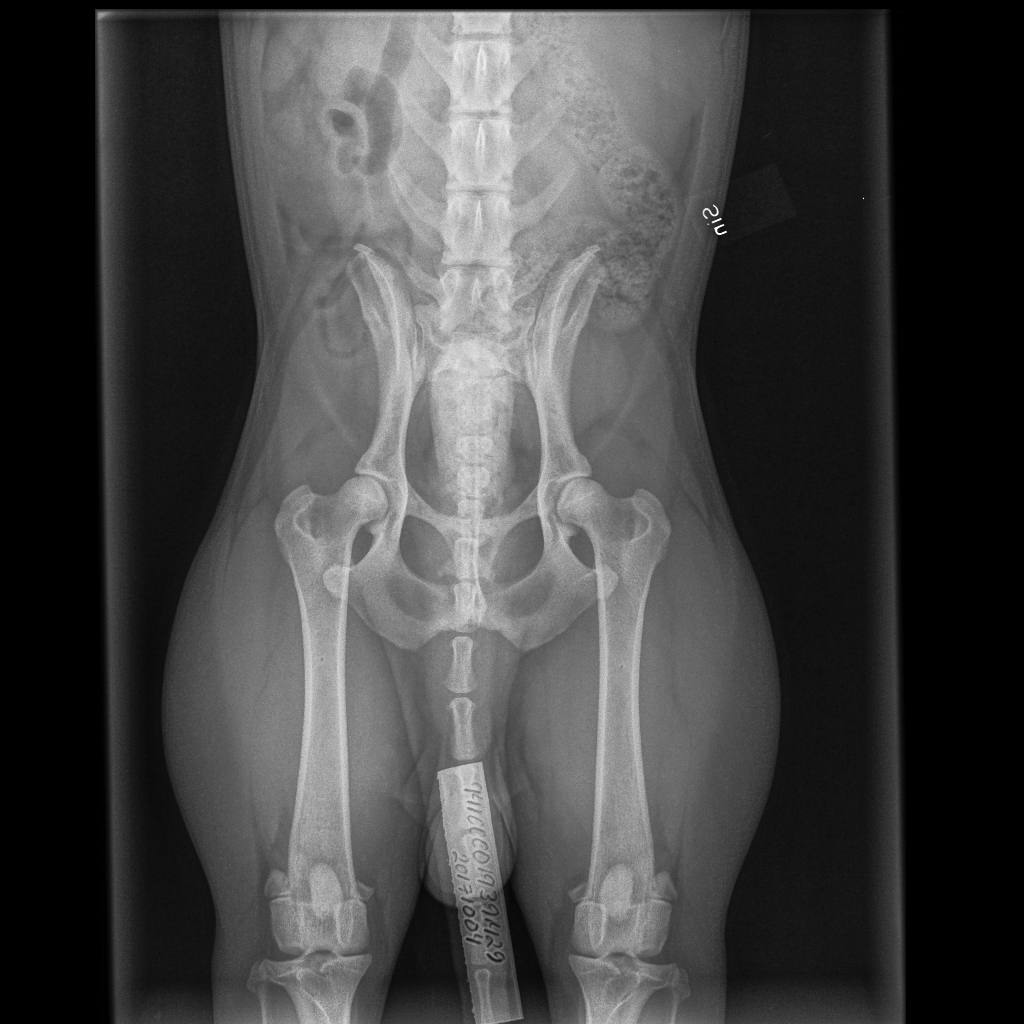

- AI-modeller analyserar röntgenbilder för att identifiera anatomiska strukturer, såsom lårbenshuvudet och höftledsskålen.

- De kan automatiskt mäta vinklar och avstånd, till exempel Norberg-vinkeln, som är en viktig parameter för att bedöma höftledens passform.

- AI-system klassificerar höftledens tillstånd enligt standardgraderingar, som A–E (enligt FCI) eller OFA:s skala.